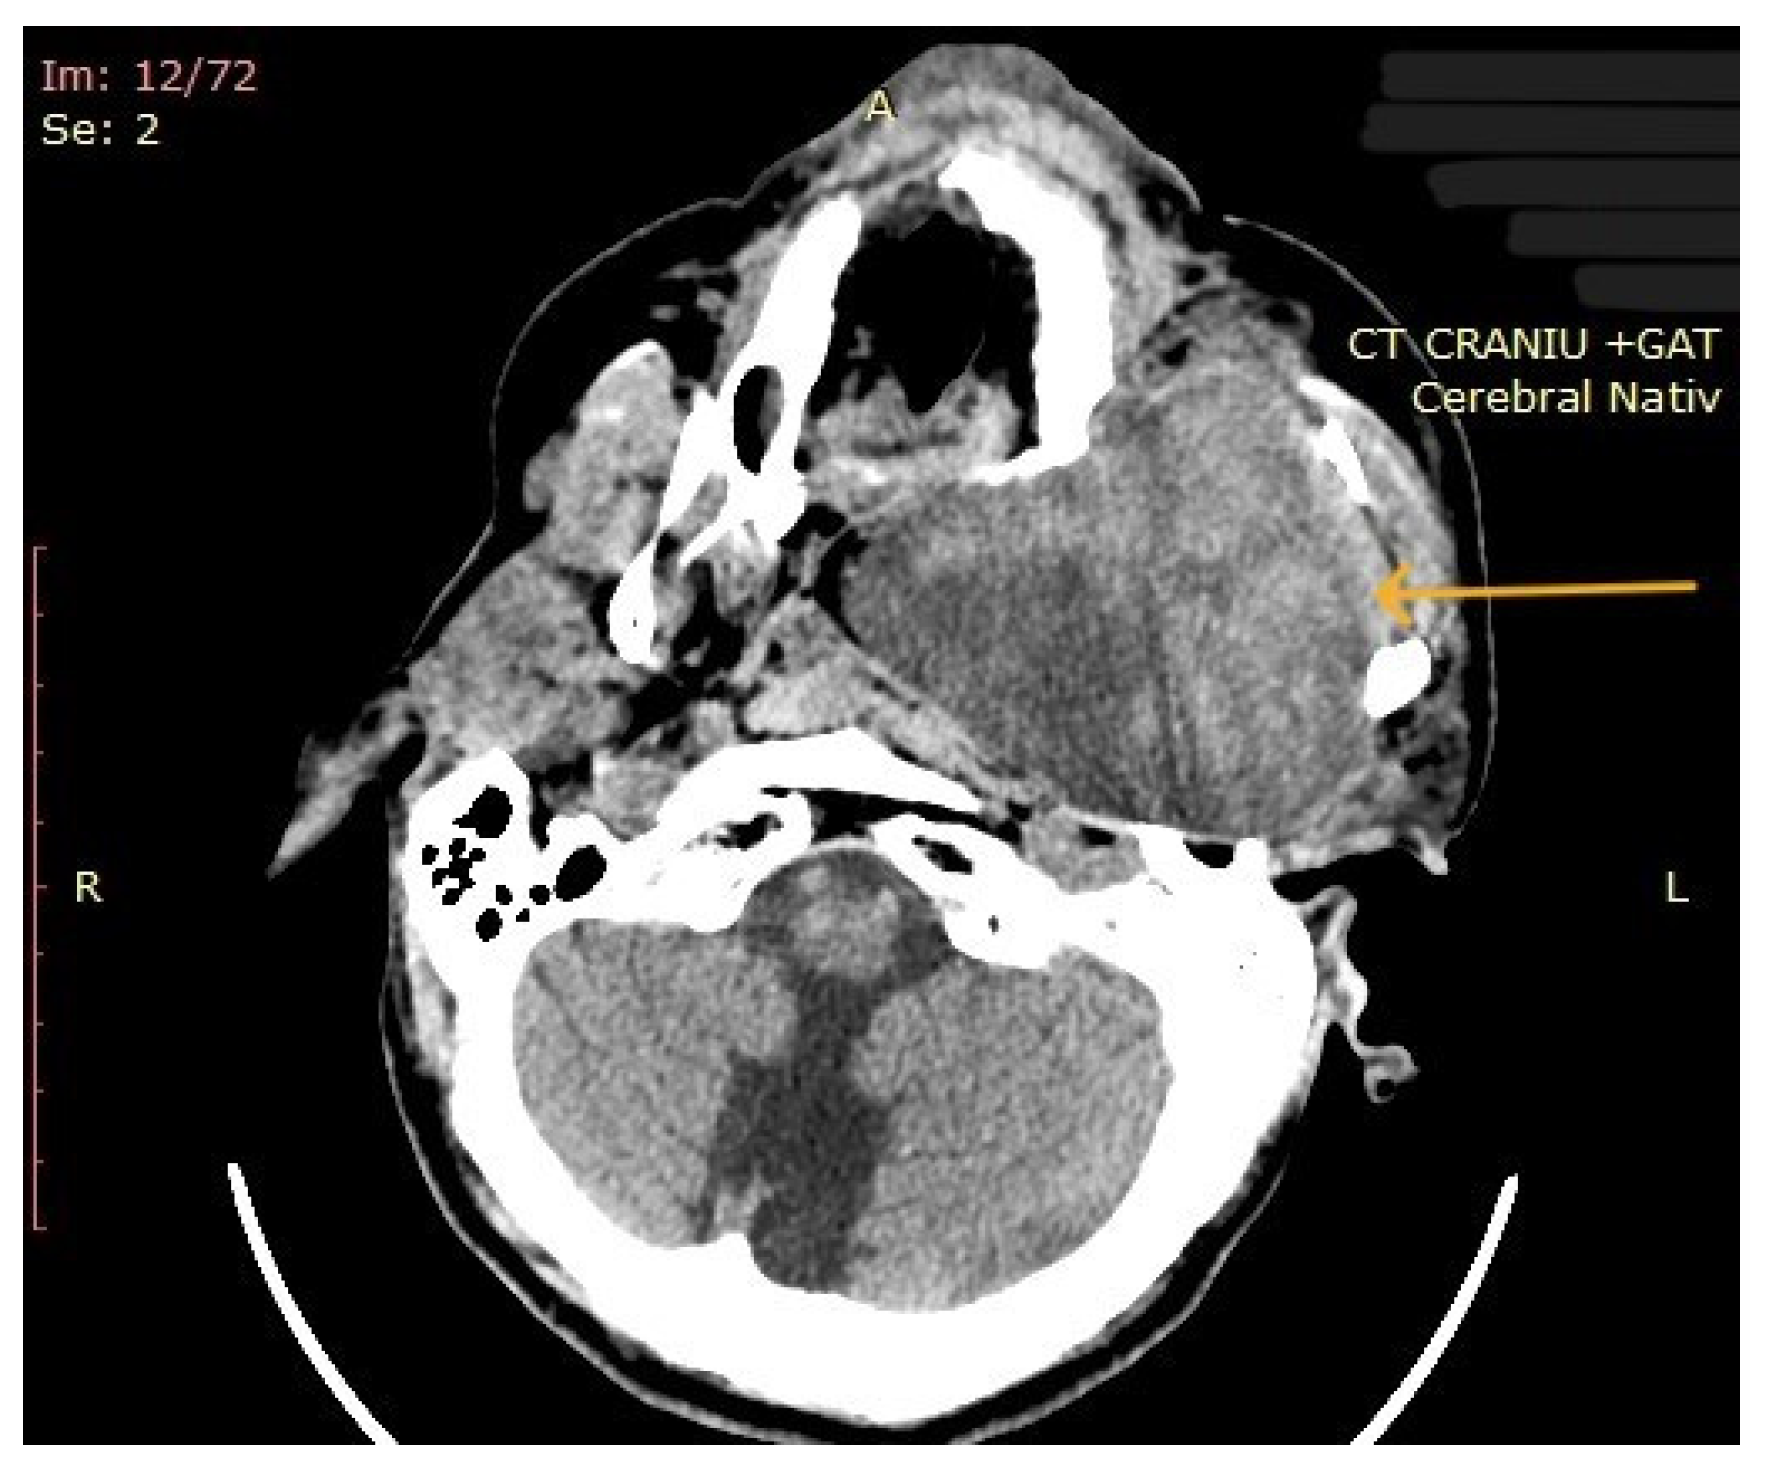

| 10 | Left parapharyngeal region with maxillary and intracranial extension | Discomfort in breathing, chewing, swallowing, phonation, sleeping, regional pain, fatigue | 5 years | 10 cm | Benign tumor of soft tissue |